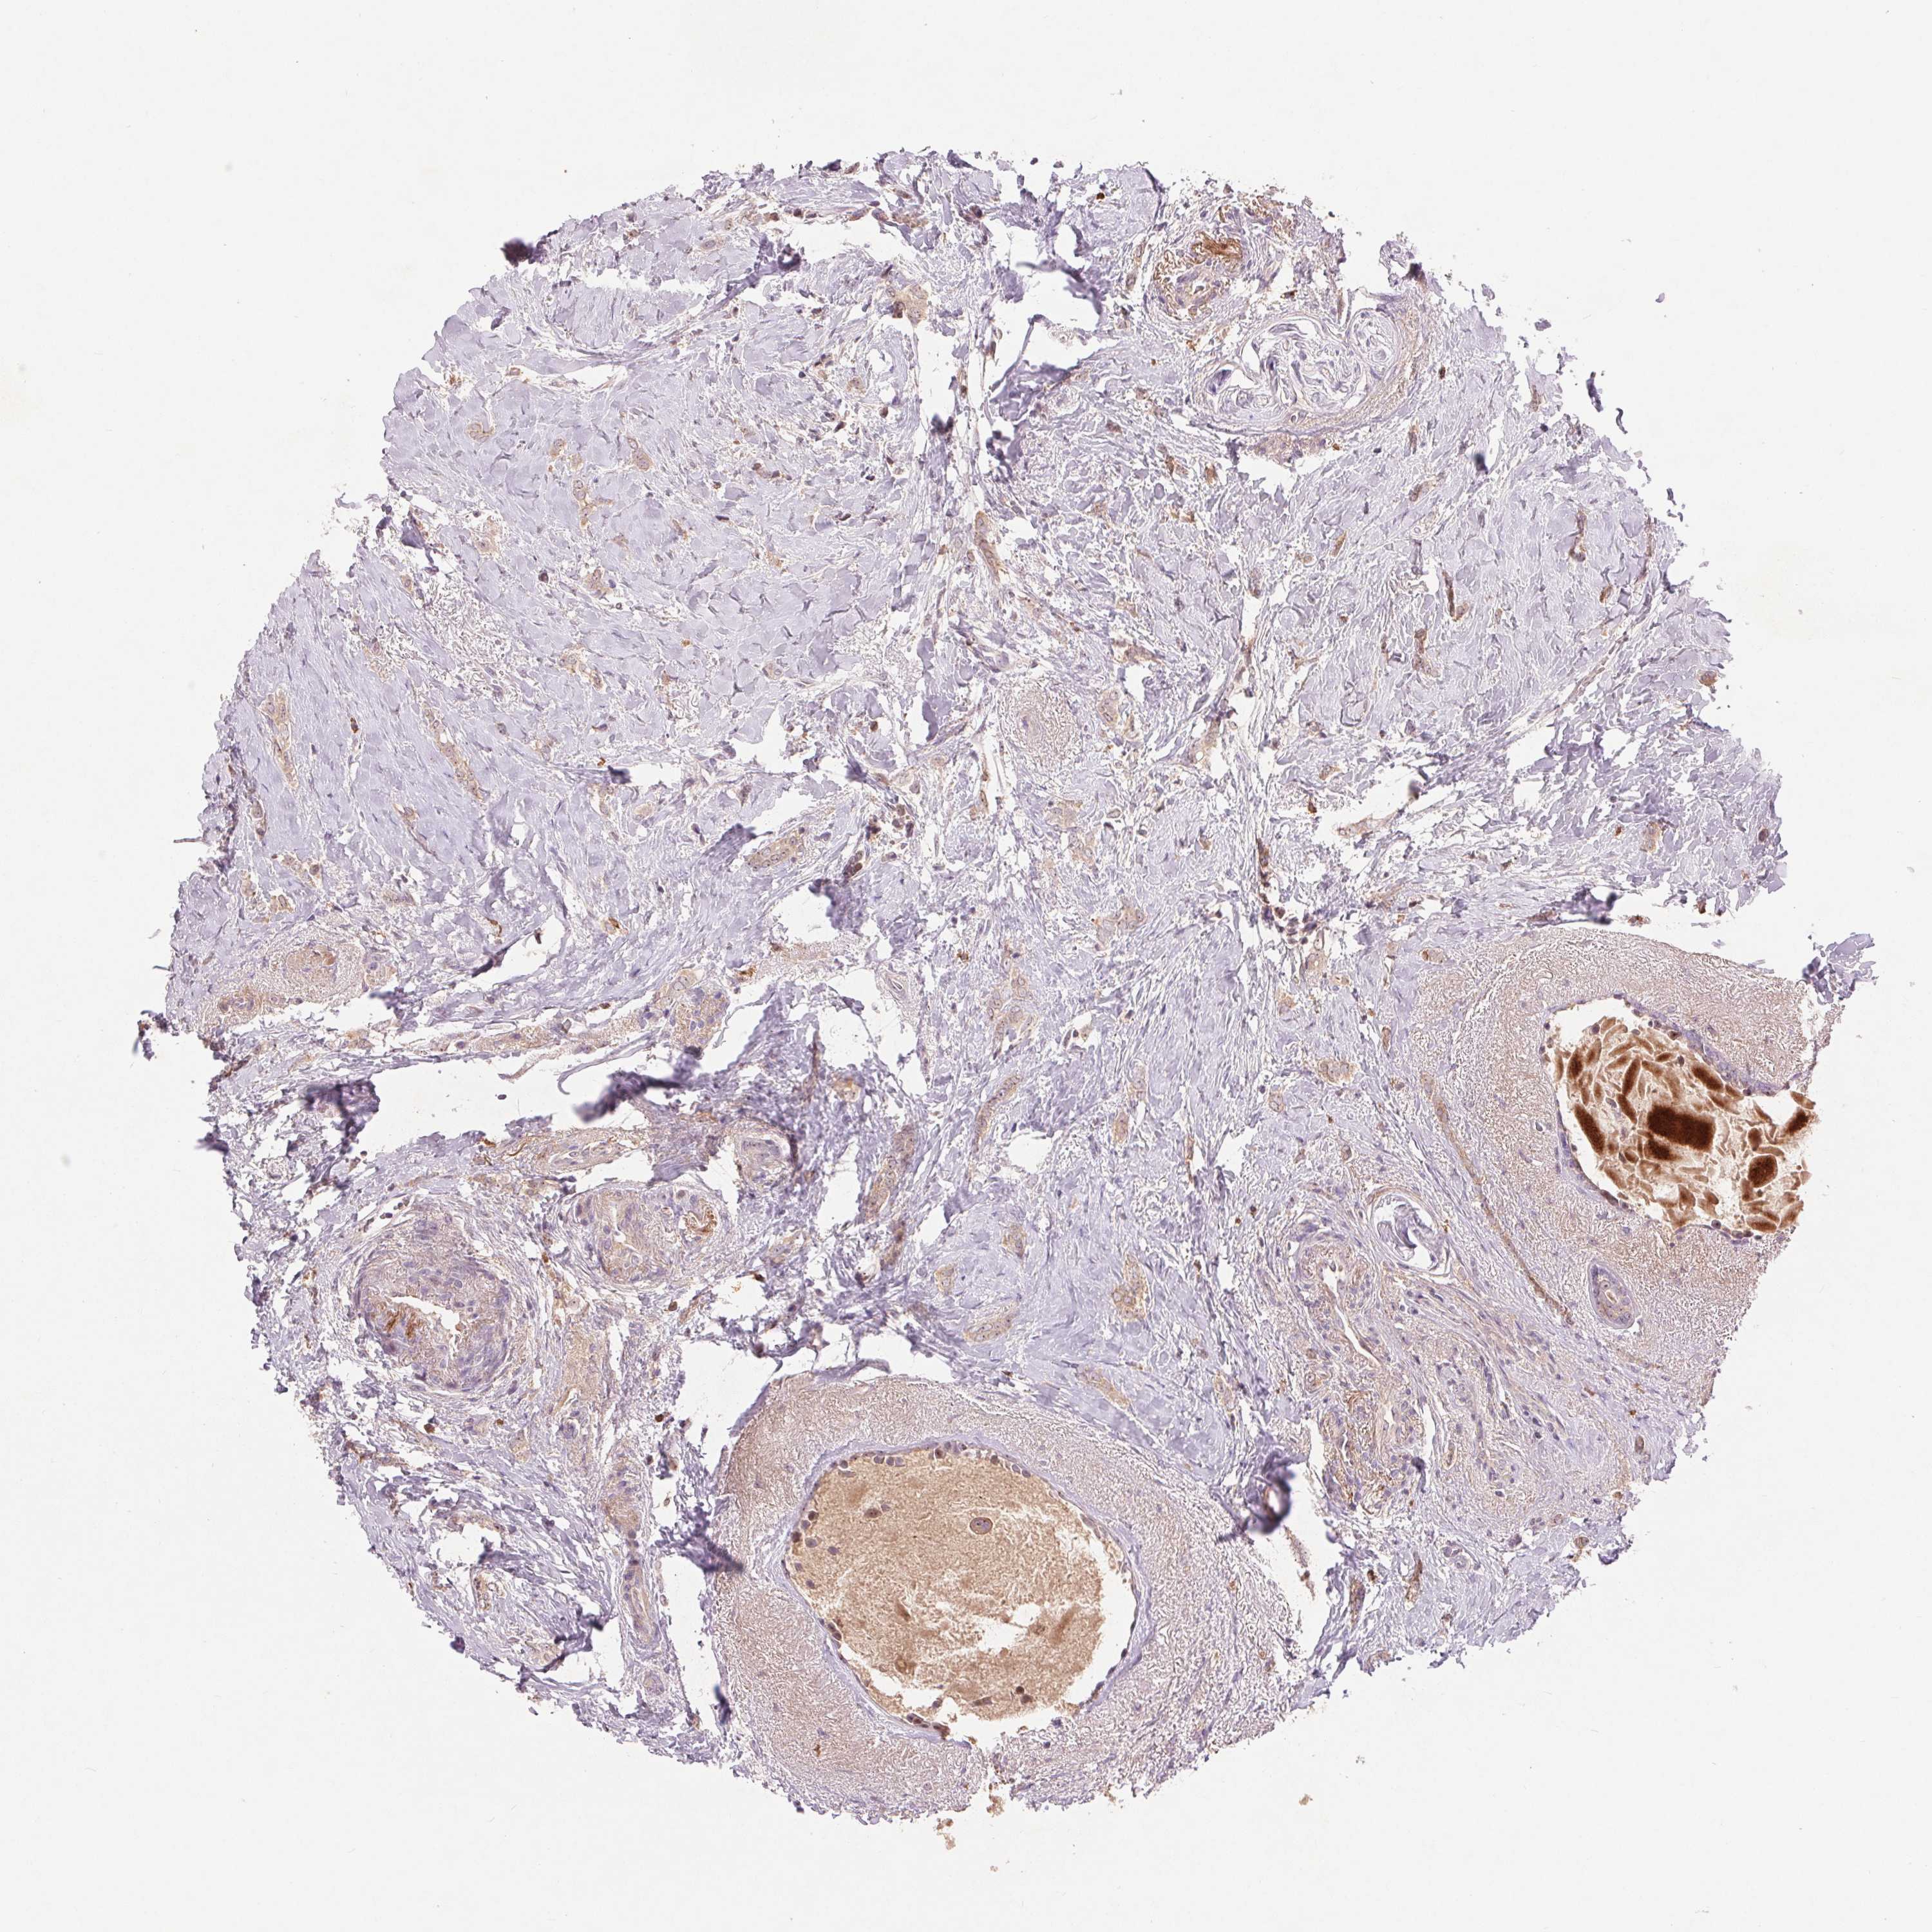

BRCA TCGA BRCA VALIDATION PROTEIN EXPRESSION

ANTIBODIES

AND

VALIDATION